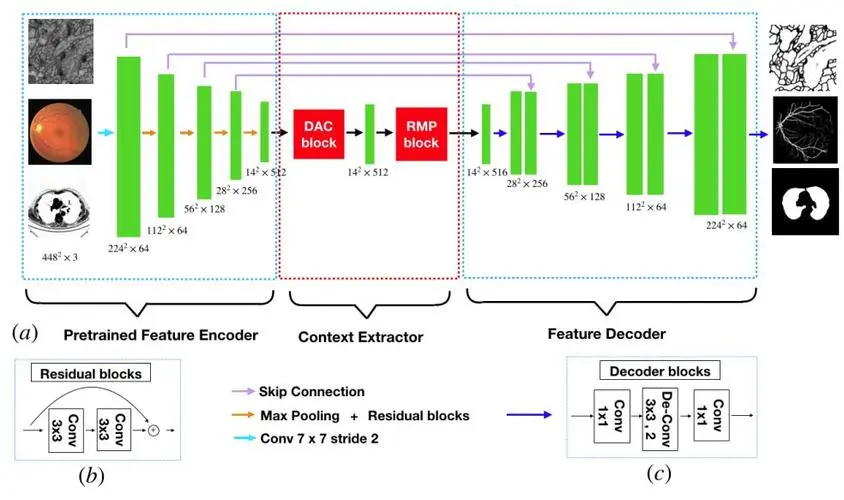

CE-Net

Paper: 《UNet++: Redesigning Skip Connections to Exploit Multiscale Features in Image Segmentation》

Accepted by TMI 2019.

CE-Net 主要包含三个主要组件,即特征编码器模块、上下文提取器和特征解码器模块。

特征编码器模块:使用预训练的 ResNet 块作为固定特征提取器;

上下文提取器模块:由密集空洞卷积(DAC)块和残差多核池(RMP)块组成,旨在来捕获更多高级信息并保留空间信息;

特征解码器模块:主要包括连续的1×1卷积,3×3转置卷积和1×1卷积,利用转置卷积学习自适应映射以恢复具有更多详细信息的特征。

综合结果表明,所提出的方法在视盘分割、血管检测、肺部分割、细胞轮廓分割和视网膜光学相干断层扫描层分割方面均取得了不错的效果。